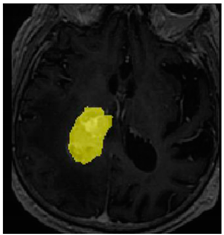

Table 2. Predictions with low dice scores.

Ground truthDeconvNetDeepMedic

Applsci 11 09180 i001 Applsci 11 09180 i002 Applsci 11 09180 i003

PSPNetU-NetV-Net

Applsci 11 09180 i004 Applsci 11 09180 i005 Applsci 11 09180 i006